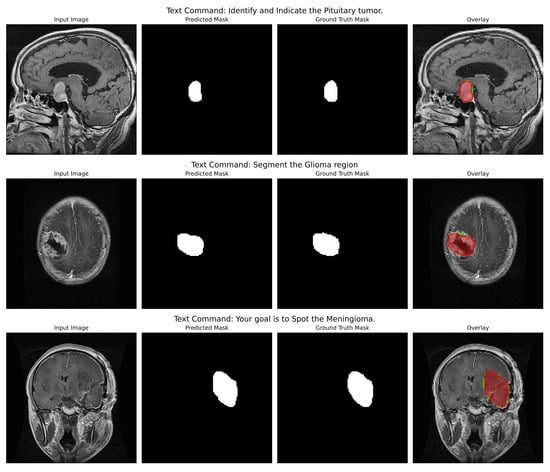

Prompt-Driven Multimodal Segmentation with Dynamic Fusion for Adaptive and Robust Medical Imaging with Applications to Cancer Diagnosis

Shatha Abed Alsaedi, Hossam Magdy Balaha, Mohamed Farsi, Majed Alwateer, Moustafa M. Aboelnaga, Mohamed Shehata, Mahmoud Badawy and Mostafa A. Elhosseini

Cancers 2025, 17(22), 3691; https://doi.org/10.3390/cancers17223691 - 18 Nov 2025

Background/Objectives: Medical image segmentation is a crucial task for diagnosis, treatment planning, and monitoring of cancer; however, it remains one of the toughest nuts to crack for Artificial Intelligence (AI)-based clinical applications. Deep-learning models have shown near-perfect results for narrow tasks such as single-organ Computed Tomography (CT) segmentation. Still, they fail to deliver under practicality, in which cross-modality robustness and multi-organ delineation are essential (e.g., liver Dice dropping to 0.88 ± 0.15 in combined CT-MR scenarios). That fragility exposes two structural gaps: (i) rigid task-specific architectures, which are not flexible enough to adapt to various clinical instructions, and (ii) the assumption that a universal loss function is best in all cancer imaging applications. Methods: A novel multimodal segmentation framework is proposed that combines natural language prompts and high-fidelity imaging features through Feature-wise Linear Modulation (FiLM) and Conditional Batch Normalization, enabling a single model to adapt dynamically across modalities, organs, and pathologies. Unlike preceding systems, the proposed approach is prompt-driven, context-aware, and end-to-end trainable to ensure alignment between computational adaptability and clinical decision-making. Results: Extensive evaluation on the Brain Tumor Dataset (cancer-relevant neuroimaging) and the CHAOS multi-organ challenge demonstrates two key insights: (1) while Dice loss remains optimal for single-organ tasks, (2) Jaccard (IoU) loss outperforms when multi-organ, cross-modality divides cancer segmentation boundaries. Empirical evidence has thus been offered that optimality of a loss function is task- and context-dependent and not universal. Conclusions: The design framework’s principles directly address what is documented in workflow requirements and display capabilities that may connect algorithmic innovation with clinical utility once validated through prospective clinical trials.

(This article belongs to the Special Issue Deep Learning and Radiomics for Cancer Diagnosis, Staging, and Treatment Response)